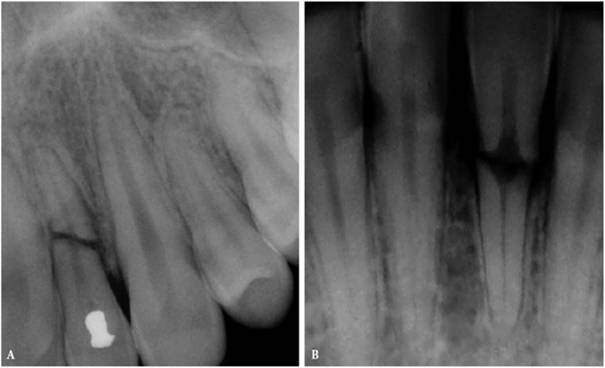

Prior to cementation, Yamada (personal communication, 2001) re-radiographs the

prepared teeth (Figures 19-25A

and B).

These images check the pulpal, periapical, and periodontal status of the teeth.

Also, the radiographs, unencumbered by the presence of the metal castings,

provide a chamber/canal road map record if the tooth requires endodontics in

the future. This may appear pessimistic, but Arens and Chivian reported that

over 40% of teeth requiring root canal therapy are crowned.4 Prior

knowledge of the size, location, and direction of the chamber and the canal will

reduce the possibility of (1) crown damage during access opening, (2) lost time

searching for the canal orifice, (3) perforations of the chamber or the canal

because of disorientation, (4) natural core elimination by gutting, (5) crown

dislodgment, and (6) sufficient destruction to alter the situation and require

corrective surgery. Each of these iatrogenic possibilities reduces the

prognosis and jeopardizes the tooth's reliability as an abutment.

Figure 19-25A and B: Precementation radiographs provide a road map to the canals if endodontic therapy is necessary after cementation of the castings. (Radiographs courtesy of Dr. Henry Yamada.)